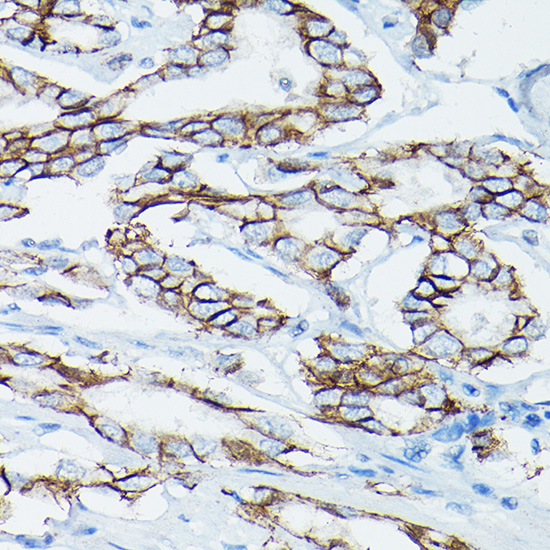

Immunohistochemistry of paraffin-embedded human liver cancer using ??-Catenin/p120 Catenin Rabbit pAb.

,

Immunohistochemistry of paraffin-embedded human prostate cancer using ??-Catenin/p120 Catenin Rabbit pAb.